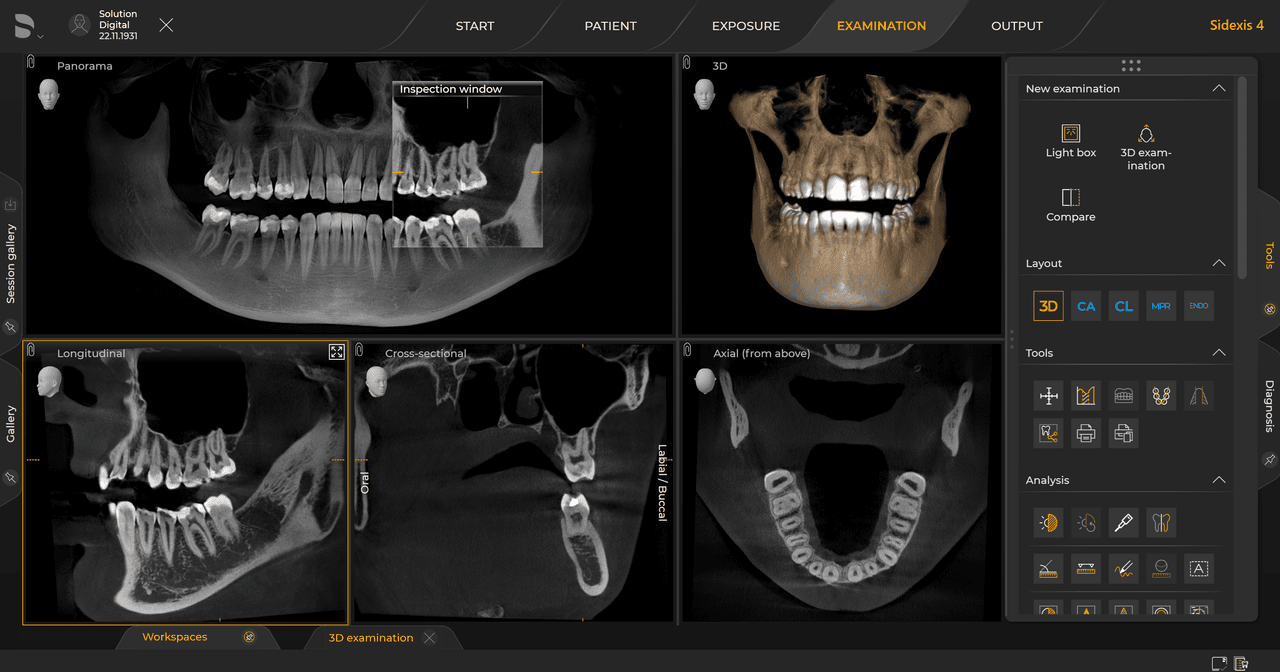

Urządzenia rentgenowskie firmy Dentsply Sirona współpracują wyłącznie z systemem Sidexis 4. Można łatwo przenieść dane z systemu Sidexis XG do systemu Sidexis 4. Sidexis 4 zapewnia pełną funkcjonalność cyfrową dzięki najnowszym narzędziom